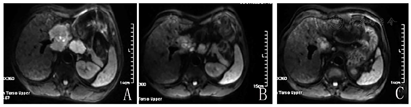

患者入科后完善相关检查。肿瘤标志物基本正常(甲胎蛋白23.2 μg/L,轻度升高)。乙肝小三阳,DNA拷贝数>105 U/ml。肝功能、血常规、凝血功能基本上在正常范围。我院肝脏超声造影提示:肝尾状叶低回声块,肝内胆管细胞癌考虑。2019年11月7日肝脏增强MRI提示:肝脏1段恶性肿瘤,考虑肝癌(肝细胞癌或混合型肝癌可能)伴门静脉主干、肝门区、肝胃间隙及右侧心膈角、腹膜后多发淋巴结转移,肝脏2段弥散加权成像见高信号小结节(图1A)。

患者因出现严重的手足皮肤反应,将索拉非尼剂量减半(0.2 g,2次/d)。治疗期间多次复查肿瘤标志物、血常规及肝功能基本正常,腹痛较之前明显好转,可停用止痛药。2020年1月6日复查肝脏MRI提示:尾状叶病灶及肝门部、腹膜后转移淋巴结稍较前缩小(10%~20%),右侧心隔角转移淋巴结增大,肝脏2段癌结节明显增大(图1B),总体疗效好。

因综合治疗效果良好,继续于2020年1月23日、2020年2月13日、2020年3月6日行3次特瑞普利单抗联合索拉非尼治疗。2020年3月9日我院再次复查肝脏MRI提示:较前片肝尾状叶癌灶及肝门部、腹膜后、右心膈角转移淋巴结缩小,肝脏2段癌结节较前增大,总体疗效好(图1C)。期间复查肿瘤标志物正常,无明显腹痛。虽然整体疗效良好,但肝脏2段肿瘤进行性增大,2020年3月12日多学科讨论建议肝脏2段肿瘤可行微波消融术,对仍偏大的右心膈角淋巴结行放疗(适形调强放疗)。2020年4月3日行肝脏2段肿瘤微波消融术,术后超声造影复查肝脏2段癌灶已消失。2020年4月30日起开始为期5周的适形调强放疗(每周5次,共计25次)。期间于2020年3月27日、2020年4月17日、2020年5月8日继续特瑞普利单抗联合索拉非尼治疗。